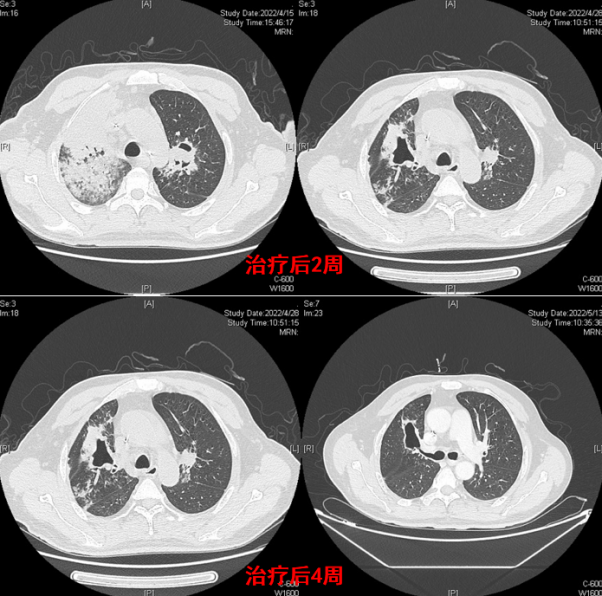

病例9:男性,49岁,主诉“反复咳嗽、咳痰、气短、痰中带血3个月”,于2022年4月27日入院。既往史:2022年1月1日大量饮酒后出现呕吐,误吸胃内容物,后出现咳嗽、咳痰,其后出现胸闷、气短,夜间不能平卧。当地乡卫生院查胸部CT:考虑左肺上叶及右肺中上叶肺炎。给予头孢类抗生素效果不佳。于2022年1月19日就诊于当地某医院,胸部CT显示两肺多发病变。在当地医院治疗一段时间后无改善,于北京某三甲医院就诊,BALF病原学和组织病理确诊毛霉病。予两性霉素B脂质体300 mg/d+泊沙康唑300 mg/d静脉滴注,治疗1个月,患者出现咯血,发热,病情加重。转入我院时胸部CT可见右上肺大片实变、坏死(图19)。气管镜下可见新生物形成,于右主支气管预置球囊防止出血,介入清创,出现支气管肺空洞瘘(图20),取出的毛霉菌丝体长约10 cm。治疗2周后复查胸部CT示右上肺病变明显缩小;治疗4周后复查可见病变处形成机化空洞(图21)。治疗期间患者出现咯血,复查支气管镜可见左侧支气管及分支仍有毛霉感染形成的新生物。支气管镜换用细探头和小球囊进一步介入清创(图22)。治疗后复查胸部CT示病变消退。

图片

19  病例9转入时胸部CT

20  病例9气管镜检查及清创

21  病例9治疗后胸部CT